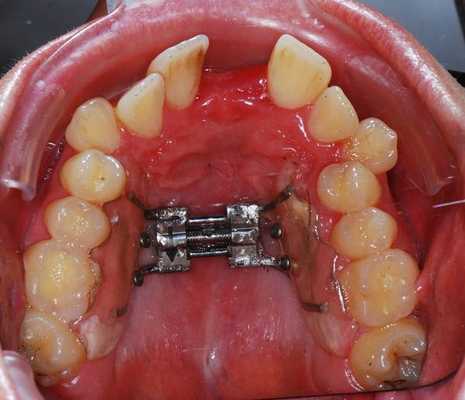

- Остеотомия небного шва или SARPE - метод, используемый для расширения верхней челюсти. В рамках лечения происходит одномоментный разрыв небного шва и впоследствии его удержание.

- Установка брекетов, чтобы выровнять зубы перед операцией. Согласовав лечение с хирургом, врач-ортодонт устанавливает брекеты пациенту, чтобы сформировать правильные зубные ряды для успешного хода операции. Срок предоперационного ортодонтического лечения определяется ортодонтом, в среднем составляет от полугода до года.

- Операция. Характер хирургического вмешательства зависит от клинической ситуации, однако все они проводятся с установленной брекет-системой.

Челюстно-лицевой хирург разрабатывает собственный план лечения и проводит необходимые расчеты в сотрудничестве с направившим пациента ортодонтом. После того, как все данные для проведения операции известны, пациент возвращается к ортодонту для подготовки к операции — лечения на брекет-системе. После того как задача выравнивания зубов и выставления их в правильный наклон выполнена, наступает момент челюстно-лицевого хирургического вмешательства. Пациент проходит операцию, не снимая брекетов.